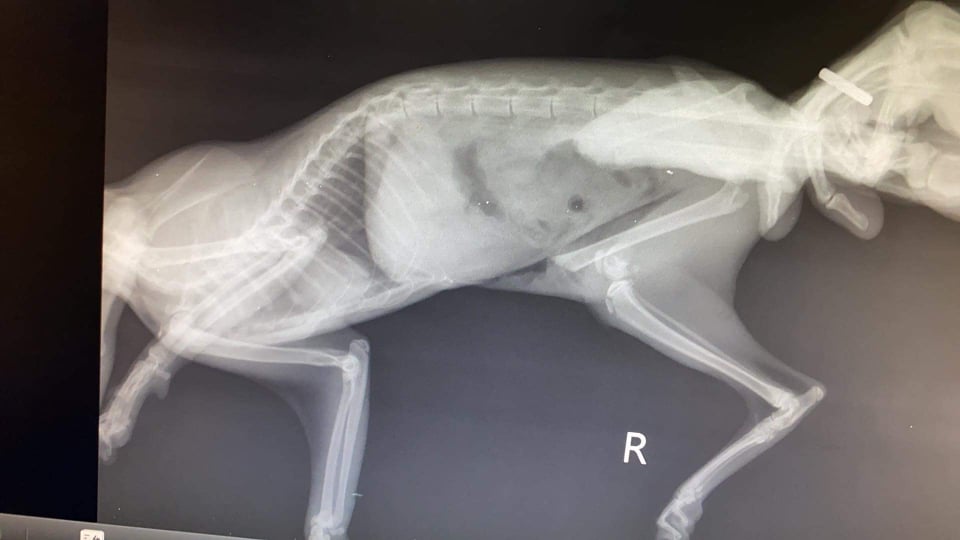

ჩვენი პატარა პრინცესა გადახტა სიმაღლიდან და აქვს მოტეხილობები. ოპერაცია ერთთან 500ლარი ჯდება, მეორე ვეტთან 400. ვისაც სურვილი გაქვთ და შეგეცოდებათ ფისო, დაგვეხმარეთ. წარმოგიდგენთ ფოტოებს.

მიმაგრებული სურათი

ჩეკი და რენტგენის ფოტოებიც წარმოვადგინე

დღეს ლინკონს ჩაუტარდა კიდევ ერთი ოპერაცია და მოტეხილი ფეხი ვერ გადაურჩა

ამპუტაცია გაუკეთდა